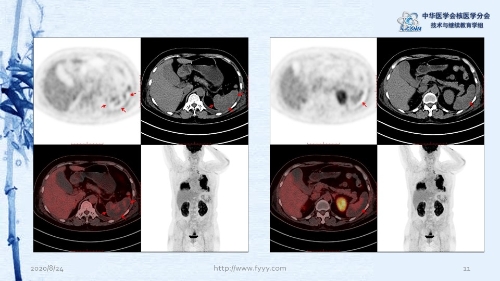

病例82:肉芽肿性血管炎PET-CT显像一例-【CSNM继教学组】郑山 福建医科大学附属第一医院